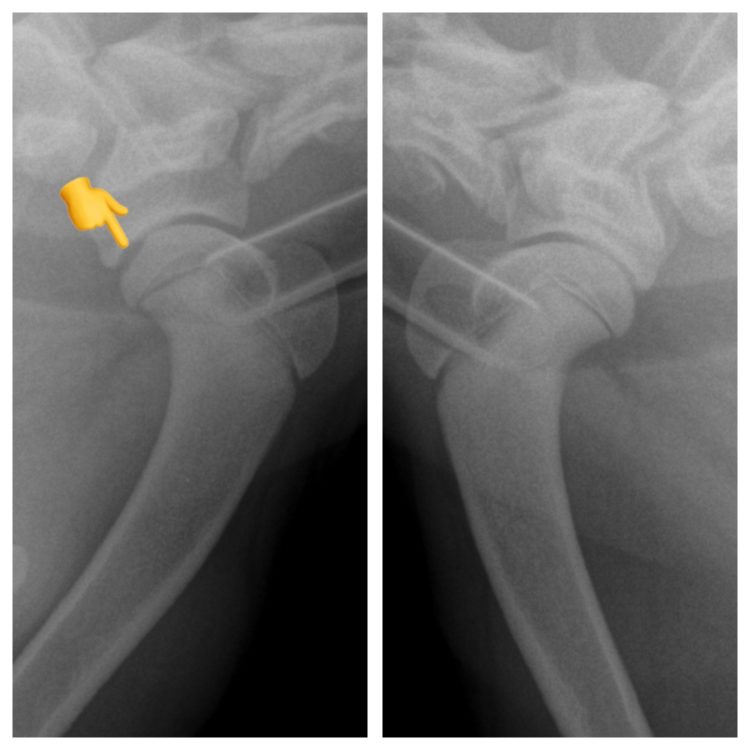

osteochondrosisshoulderdog Walkerville Vet What Can You Give A Dog For Shoulder Pain learn about shoulder injuries in dogs, recognize the signs of pain and discomfort, and discover the. fortunately, there are many medical, supplemental, and holistic treatments that can provide reliable pain relief for dogs. In this article, we’ll discuss. what pain meds can i give my dog? Unusual postures can indicate pain. you can only give your. What Can You Give A Dog For Shoulder Pain.